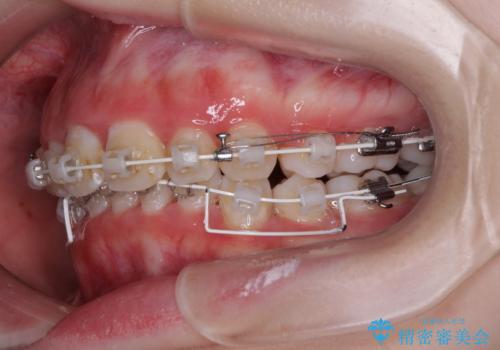

- 矯正装置

- 審美装置

下顎前歯が隠れるほどのディープバイトであり、それによる顎の負担も大きかったため、ディープバイトもしっかりと改善できるよう、表側のワイヤー装置にて矯正治療を行うこととしました。